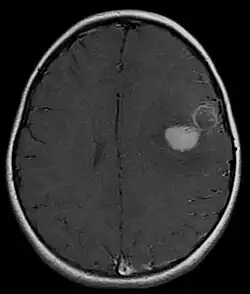

Magnetic resonance image of PNET

Several analysis can be used to determine the presence of the disease. Physical examinations showing papilledema, visual field defects, cranial nerves palsy, dysphasia, and focal neurological deficits are evidences for possible tumor.[2] PNETs can also be spotted through computed tomography (CT) and magnetic resonance imaging (MRI).[2] In images produced by MRIs, an irregular augmentation among a solid mass will indicated the presence of tumor.[3] However, the results of MRIs are usually ambiguous in defining the presence for this specific tumor.[2] In CT scans, the presence of PNETs will be indicated by an elevated density and an increase in volume of the brain.[2] The CT scan can also show calcification,[3] which is present in 41-44% of PNET cases.[2] Since the tumor can be replicated in other parts of the nervous system through the cerebrospinal fluid (CSF), a CSF analysis can also be conducted.[2] A spinal MRI is a fourth type of analysis that is useful in investigating the level of tumor propagation to the spinal cord.[2]